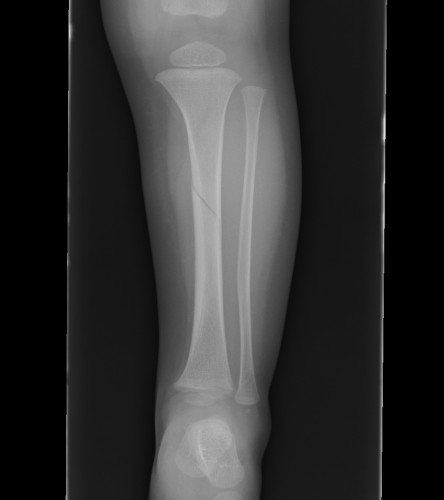

Displaced Tibial Shaft Fractures

Acceptable reduction

- varus / valgus < 5o

- anterior / posterior < 5o

- rotation 5o

- shortening 10 mm